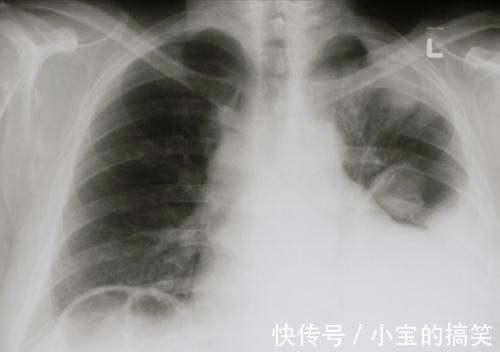

疾病|肺癌最可怕的不是疾病本身,而是伴随的并发症

癌症并发症是指在自然病程发展过程中,肿瘤发生侵犯、转移到某些脏器,或者是在治疗过程中因手术、放化疗而难以避免所产生的一系列综合病症,某些癌症并发症是患者首发症状。

广州中医药大学金沙洲医院国际肿瘤医疗中心毛迪生教授提到:癌症并发症对患者的生命、生活质量均会产生不同程度的影响,严重的并发症甚至是肿瘤患者的主要死因,约有80%-90%的病人死于肿瘤并发症,而非肿瘤本身。

肺癌患者常见的并发症有哪些?

1、恶性胸腔积液

胸腔积液在肺癌中的发生率约为 7~23%,其中恶性胸腔积液约占胸腔积液的 90~95%,患者主要表现为进行性加重的呼吸困难、胸痛和干咳。呼吸困难的程度与胸腔积液量的多少、胸液形成的速度和患者本身的肺功能状态有关。

当积液量少或形成速度缓慢,患者呼吸困难较轻,仅有胸闷、气短等;若积液量大则肺脏受压明显,患者呼吸困难程度加重,甚至可能出现端坐呼吸、发绀等。